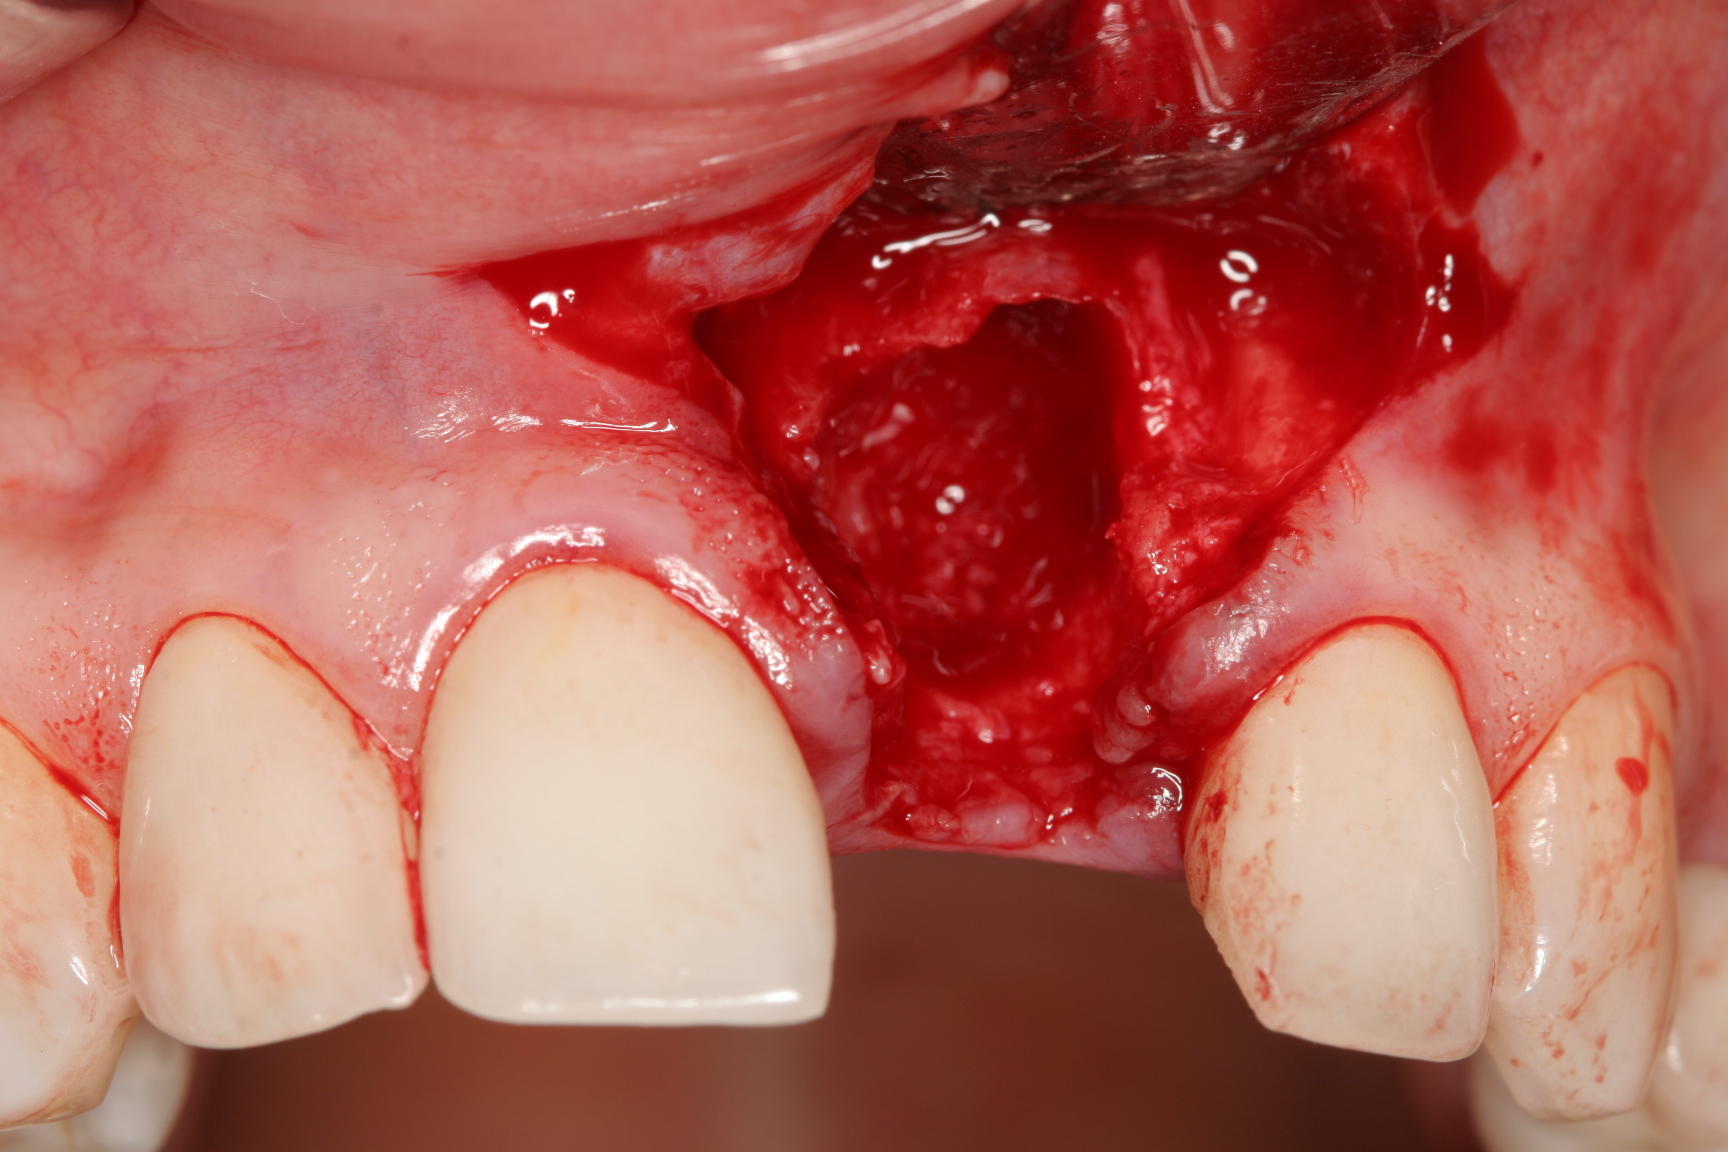

How to handle “Disasters in the esthetic  zone” and come out on top

You can’t handle major diasasters like the missing buccal plate or other disastes  without these strategies and tactics. Enter your info to watch the webinar for free now.